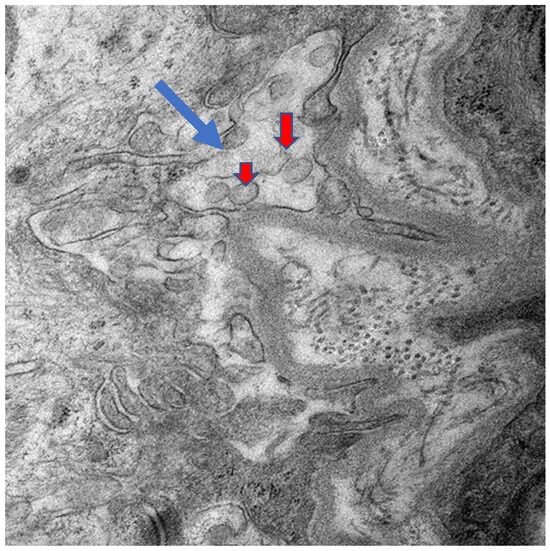

Placental Autophagy Modulation and Ultrastructural Changes in COVID-19 Patients: A Pilot Study Using Immunohistochemistry and Transmission Electron Microscopy

Background: Autophagy is a conserved intracellular degradation pathway essential for maintaining cellular homeostasis by recycling damaged organelles and proteins. Dysregulation of autophagy has been implicated in pregnancy-related complications such as preeclampsia and fetal growth restriction, underscoring its importance in maternal and fetal health. However, the autophagy status in the placental tissue of COVID-19-infected pregnant women remains unknown. Objective: To investigate autophagy activity in term placentas from pregnant women infected with COVID-19 compared to those from uninfected control pregnant women. Methods: In this prospective cross-sectional single-center study, 15 COVID-19-positive and 15 COVID-19-negative term pregnant women who delivered at Sultan Qaboos University Hospital between January 2020 and December 2022 were included. Immediately after delivery, the placental tissue samples were collected and assessed for autophagy activity using immunohistochemistry for LC3B and p62 markers, histopathological examination, and transmission electron microscopy. The proportion and intensity of LC3B and p62 staining were quantified. Statistical analysis was performed using the Mann–Whitney U test. Results: There was a significant reduction in p62 and LC3B expression in both the proportion and intensity in COVID-19 placentas compared to the control group. The proportion of p62 (p = 0.001) and LC3B (U = 46.000, p = 0.003) was significantly reduced in infected placentas. Similarly, intensity levels of both markers showed significant differences (p < 0.05), supporting the evidence of reduced LC3B/p62, suggesting autophagy modulation in COVID-19 patients’ placentas. Additionally, abnormal ultrastructural changes were observed in COVID-19–positive placentas, including mitochondrial injury, endoplasmic reticulum stress, microvillus loss, and basement membrane thickening. Conclusion: The study results from a limited sample size demonstrate a significantly altered autophagy flux in the placental tissues of term pregnant women with COVID-19 infection. These findings highlight the potential impact of COVID-19 infection on placental function and fetal development and underscore the need for further investigation into autophagy-modulating strategies to improve maternal–fetal health. Full article